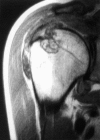

Amyloid, advanced glycation end products, and dialysis related arthropathy